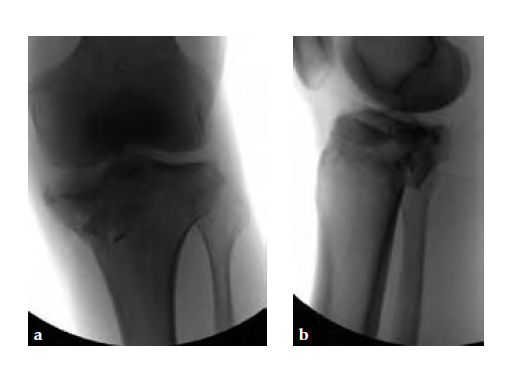

A 33-year-old male was involved in an altercation and suffered a gun shoot wound to his knee

Initially taken for incision and drainage and then ORIF . Patient placed in a floppy lateral position with the effected lower extremity externally rotated (opposite hip and shoulder bumped up about 3040) allowing exposure of the posterior medial knee. A posterior medial and an anteromedial incision were used to repair the fracture with a 67 cm skin bridge.